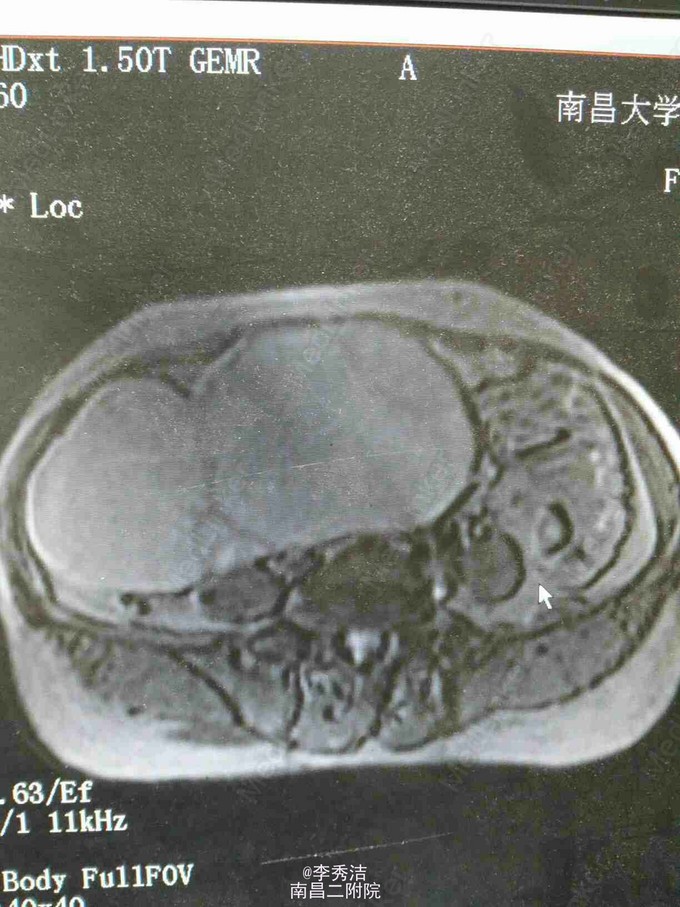

患者64岁,因“下腹部疼痛不适3月”入院。

查体:腹隆,可及一实性包块,上界平脐,下界至耻骨联合,两侧达腹直肌外缘,活动欠佳,无压痛。妇科检查:外阴:萎缩,阴道:畅,潮红,少许淡黄色分泌物,异味重。宫颈萎缩,宫体扪不清,盆腔扪及一巨大包块,达脐,如孕4月子宫大小,活动差,无压痛,实性,肛诊:于直肠前壁距肛门约7㎝处可及一外压性肿块,实性,质硬,指套无血染,直肠粘膜光滑。糖类抗原CA125-36.00U/mL。我院盆腔磁共振示盆腹腔巨大多房囊性占位,考虑附件来源肿瘤病变,粘液性囊腺瘤可能。